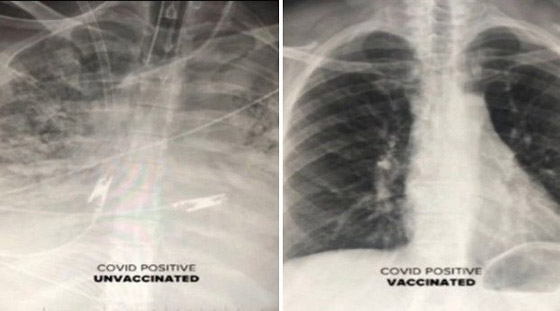

كشفت صور جديدة بالأشعة السينية عن الفرق الكبير بين رئتي الأشخاص الذين حصلوا على لقاح كورونا والذين لم يحصلوا على اللقاح.

وأوضح الدكتور دوراني أن المرضى الذين تم تطعيمهم والذين أصيبوا بفيروس كورونا لديهم المزيد من الهواء المتدفق إلى رئتيهم، مع تلوين الجزء الأكبر من الرئتين باللون الأسود في الفحص، وهذا يعني أن هناك ضررًا ضئيلًا جدًا أو لا يوجد ضرر على الرئتين. وتظهر صورة الفحص من شخص غير محصن أن الرئتين محتقنتان للغاية، مما يحد من تدفق الأكسجين في جميع أنحاء الجسم.